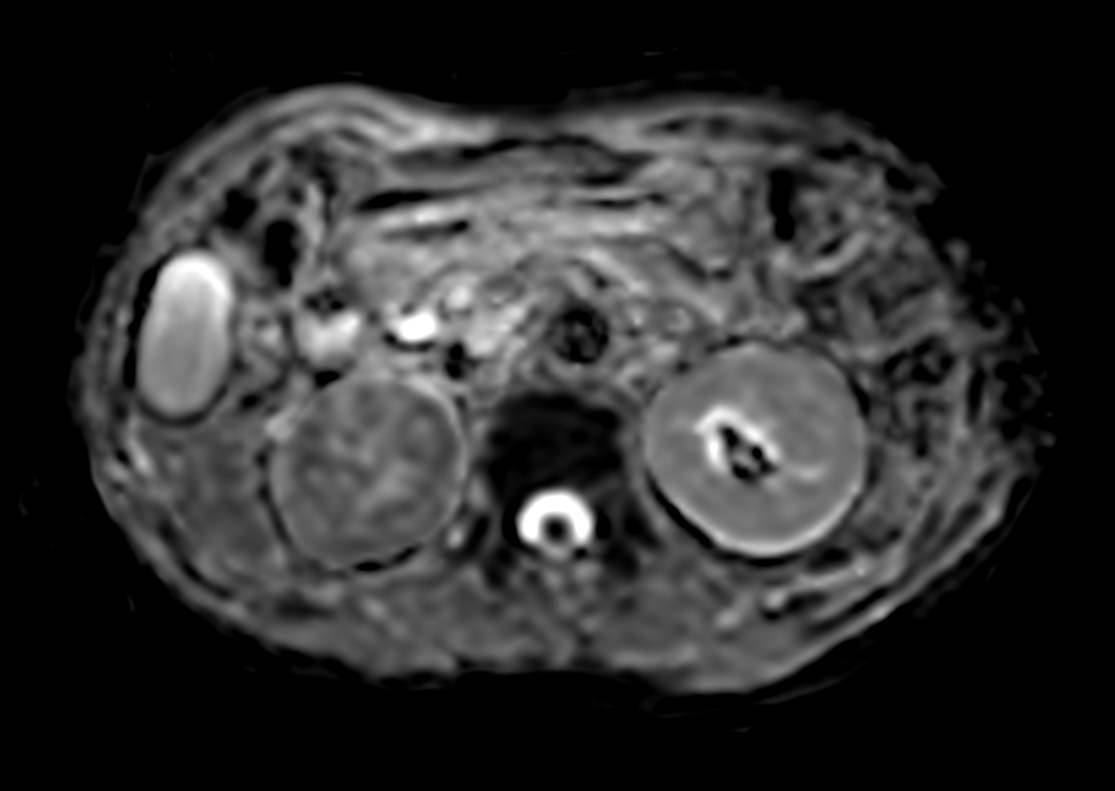

Patient with a kidney lesion. The ExamCard includes techniques for 3D imaging (PelvisVIEW, eTHRIVE) allowing for multiple image directions in one single scan, efficient fat-free imaging over large field-of-views (mDIXON XD), a multi-phase contrast-enhanced sequence (4D FreeBreathing) to improve imaging confidence and Compressed SENSE to accelerate the entire exam.

DWI b800 (ADC)